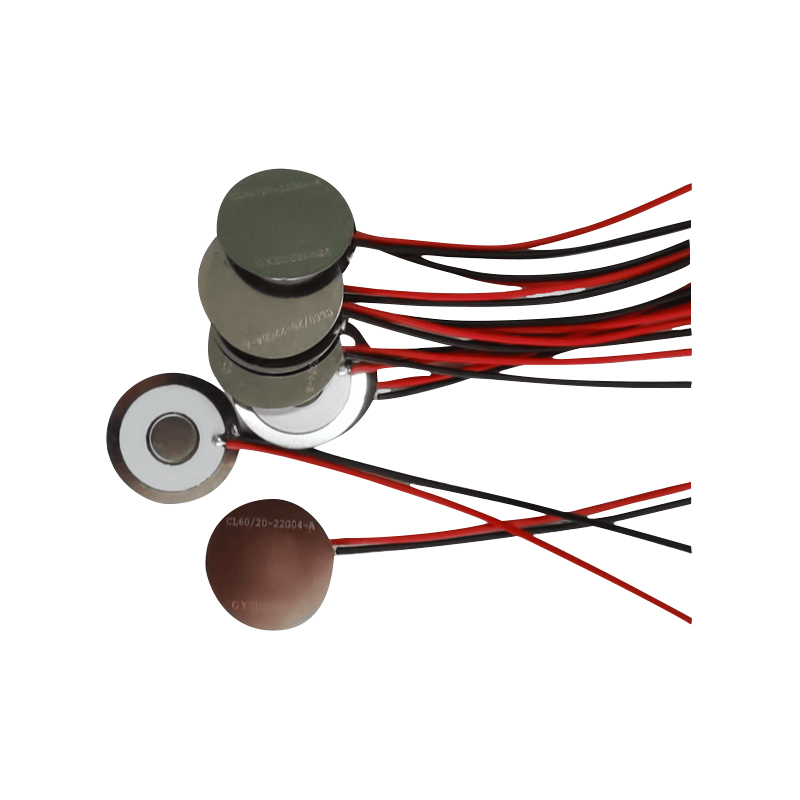

Medyczne tabletki do nebulizatora siatkowego to precyzyjne elementy stosowane w urządzeniach medycznych do przekształcania leków lub roztworów w drobne cząsteczki aerozolu w celu leczenia różnych chorób układu oddechowego, takich jak astma i przewlekła obturacyjna choroba płuc (POChP) itp., poprzez inhalację. Konstrukcja i dobór materiału arkusza nebulizatora mają kluczowe znaczenie dla zapewnienia skutecznego podawania leku i komfortu pacjenta. Arkusz membrany ze stali nierdzewnej jest dziurkowany w blasze stalowej tysiącami drobnych otworów o oczkach 2-3 μm za pomocą technologii wiercenia laserowego w precyzyjnym procesie laserowym, a następnie jest ściśle połączony z okrągłym arkuszem ceramicznym piezoelektrycznym, który przekształca częstotliwość rezonansową arkusza piezoelektrycznego w energię wibracji o wysokiej częstotliwości poprzez sygnał wyjściowy płytki sterownika PCB i szybko rozkłada płynny lek na drobne cząsteczki aerozolu. Krople te nazywane są również medianą wielkości cząstek. Gdy mediana wielkości cząstek D50 osiąga >60% lub więcej, cząstki będą wystarczająco małe, aby podczas oddychania móc dotrzeć głęboko do płuc do powierzchni pęcherzyków płucnych, poprawiając w ten sposób skuteczność wchłaniania leku i efekt terapeutyczny. Arkusz nebulizatora z mikrosiatką medyczną ma głównie kilka form, arkusz nebulizatora z mikrosiatką ze stali nierdzewnej, arkusz nebulizatora medycznego z niklowo-palladem, arkusz nebulizatora medycznego z polimeru PI i tak dalej. Wszystko powyższe odbywa się poprzez piezoelektryczną konwersję energii wibracji ceramicznych w celu osiągnięcia efektu atomizacji.

Bezołowiowa ceramika piezoelektryczna jest znana jako „perła” przemysłu piezoelektrycznego, w przyszłości stopniowo zastąpi ona we wszystkich aspektach ceramikę piezoelektryczną na bazie ołowiu, która ma już tę samą wydajność piezoelektryczną, oraz blachę piezoelektryczną na bazie ołowiu. Jest całkowicie nietoksyczny, nieszkodliwy, bezpieczny i przyjazny dla środowiska, nie zawiera ołowiu, antymonu i innych metali ciężkich oraz innych pierwiastków objętych ograniczeniami Rohs, wysoka temperatura Curie Tc-328°C, bardzo niska strata elektryczna TangentLoss Dlatego bezołowiowy piezoelektryczny chip do atomizacji medycznej ma wielką wartość handlową i wartość uniwersalną, naprawdę nietoksyczną i przyjazną dla środowiska, bezołowiową ceramikę piezoelektryczną, a także niezanieczyszczającą, piezoelektryczną wydajność porównywalną z ceramiką na bazie ołowiu, stanie się popularną przyjazną dla środowiska ceramiką piezoelektryczną. Po latach badań i rozwoju, po ciągłych testach i eksperymentach, firmie udało się wyprodukować bezołowiowy medyczny chip atomizujący, który pozwala uzyskać taką samą ilość atomizacji jak chip atomizujący na bazie ołowiu, a także wymagania dotyczące cząstek o tej samej średnicy. Bezołowiowy chip nebulizatora medycznego Mesh z pewnością zabłyśnie i znajdzie szerokie zastosowanie.